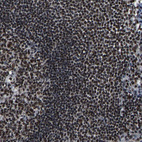

Immunohistochemical staining of human cerebral cortex, gastrointestinal, kidney and lymphoid tissues using Anti-LUC7L3 antibody HPA018475 (A) shows similar protein distribution across tissues to independent antibody HPA018484 (B).